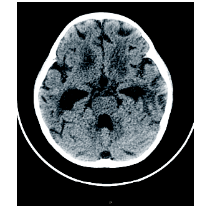

周正根(影像科主治医师):根据患儿的影像学图片介绍一下TBM的影像学特点, 首先, TBM比较容易出现脑积水, 见图1, 在脑底部的脑池可见分泌物, 脑室壁增厚; 其次, 脑室、脑沟可见到钙化, 见图2和图3, 钙化灶对结核的诊断有一定意义; 第三, 由于TBM可能侵犯到小血管, 所以可以见到一些低密度的梗塞病灶。